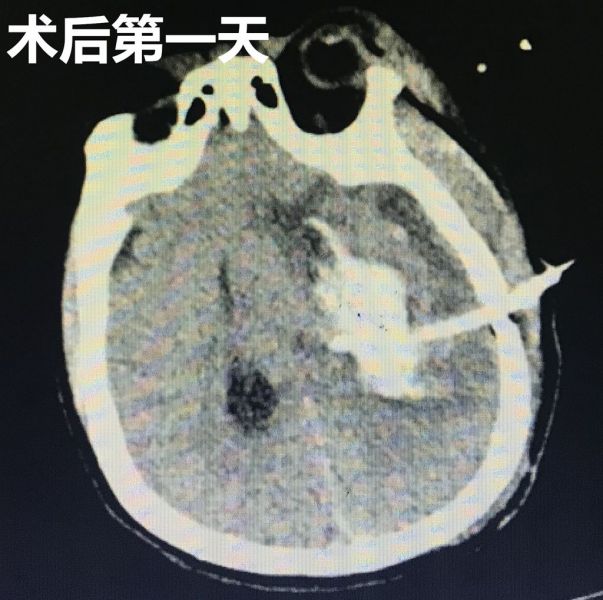

术后复查CT显示穿刺引流管位置良好。通过三天的引流血肿,再次复查CT显示颅内血肿已大部分清除,患者术前受压的脑组织也基本回位,病人的意识状态也比术前明显好转。目前患者病情稳定,正积极康复治疗中。

术后复查CT结果